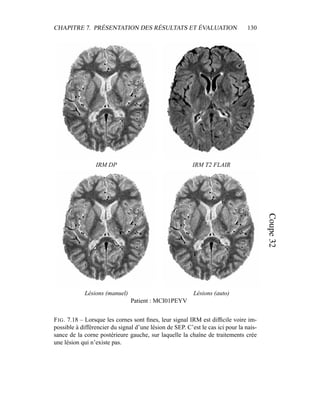

G. Malandain. Automatic segmentation of white matter lesions in multi-

sequence MRI of relapsing-remitting multiple sclerosis patients. In 21st

Congress of the European Committee for Treatment and Research in Mul-

tiple Sclerosis (ECTRIMS), Thessaloniki, September 2005.